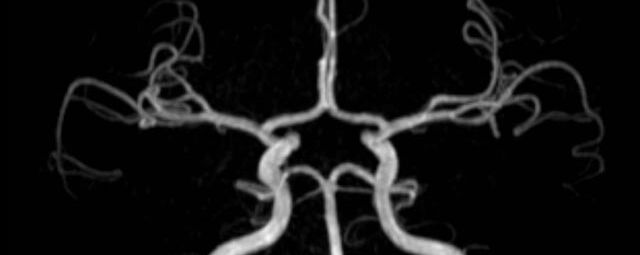

• intrakranielle Gefäße (Abklärung Verschluss, Stenose, Aneurysma)

• Halsgefäße zur Therapieplanung (z.B. Stent, Operation)

MR-Angiografie (MRA)

• MR-Angiografie ohne Kontrastmittel

• Time of Flight (TOF)-Angiographie

Je nach Fragestellung und Körperregion Gefäßdarstellung ohne Kontrastmittel bei Kontrastmittelunverträglichkeit oder terminaler Niereninsuffizienz möglich.

• MR-Angiographie mit Kontrastmittel

• Erfassung arterieller und venöser Gefäße/Bypässe aller Körperregionen mit 3D-Rekonstruktion